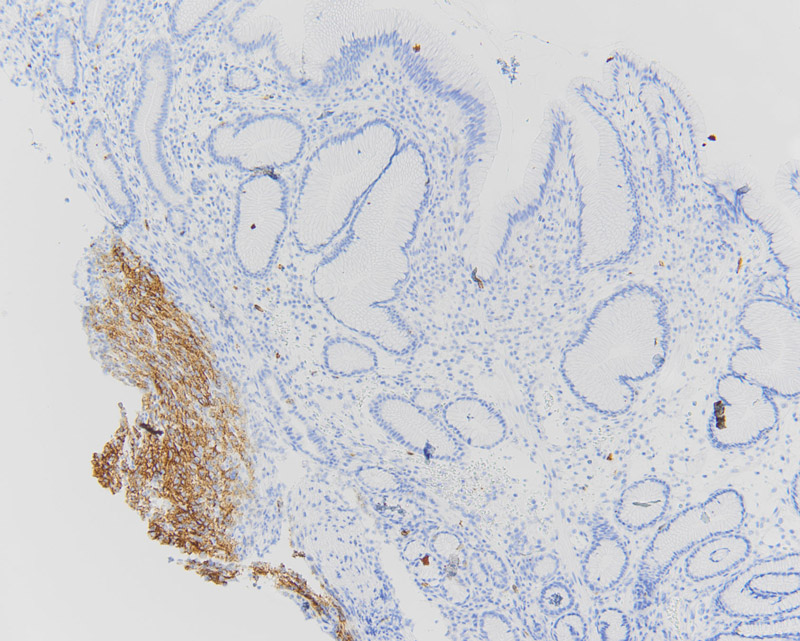

The polyp was non-obstructing and not actively bleeding; biopsies were taken of this polyp. Histologically the biopsy specimen demonstrated a proliferation of uniform mixed epithelioid and spindle-epithelioid cells amongst antral-type mucosa (Figures 2, 3). No significant pleomorphism or mitotic figures were identified. Immunohistochemical stains for DOG1 and c-Kit (CD117) were positive (Figures 4 and 5, respectively). A subsequent wedge resection of the stomach to include the lesions was performed and confirmed the original biopsy diagnosis (Figure 6). Molecular testing for c-Kit and PDGFRA were performed and were negative.